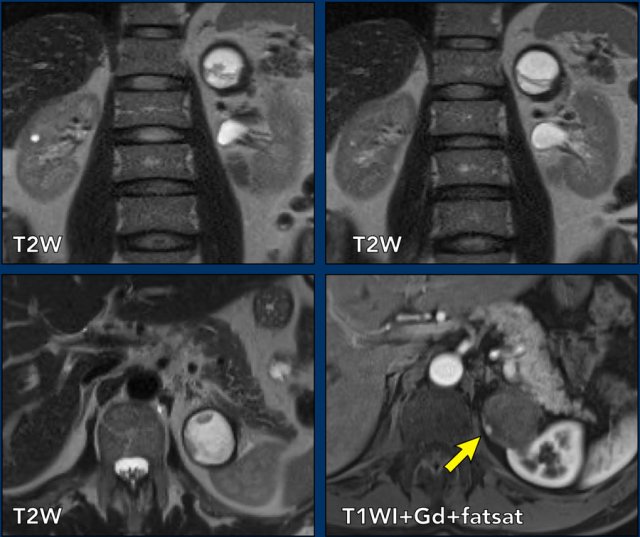

case 3

The axial and coronal T2 images show a cystic lesion within the lower pole of the left kidney with a thickened irregular wall.

As less than 25% of the lesion is comprised of solid tissue, the lesion should be classified as a cystic mass instead of a cystic solid renal tumor.

In the pre- and post-contrast coronal T1 fat suppressed images a wall thickness of more than 4 mm was measured (arrow).

The lesion was classified as a Bosniak IV cystic mass.

The mass was excized and proved to be a clear cell carcinoma.